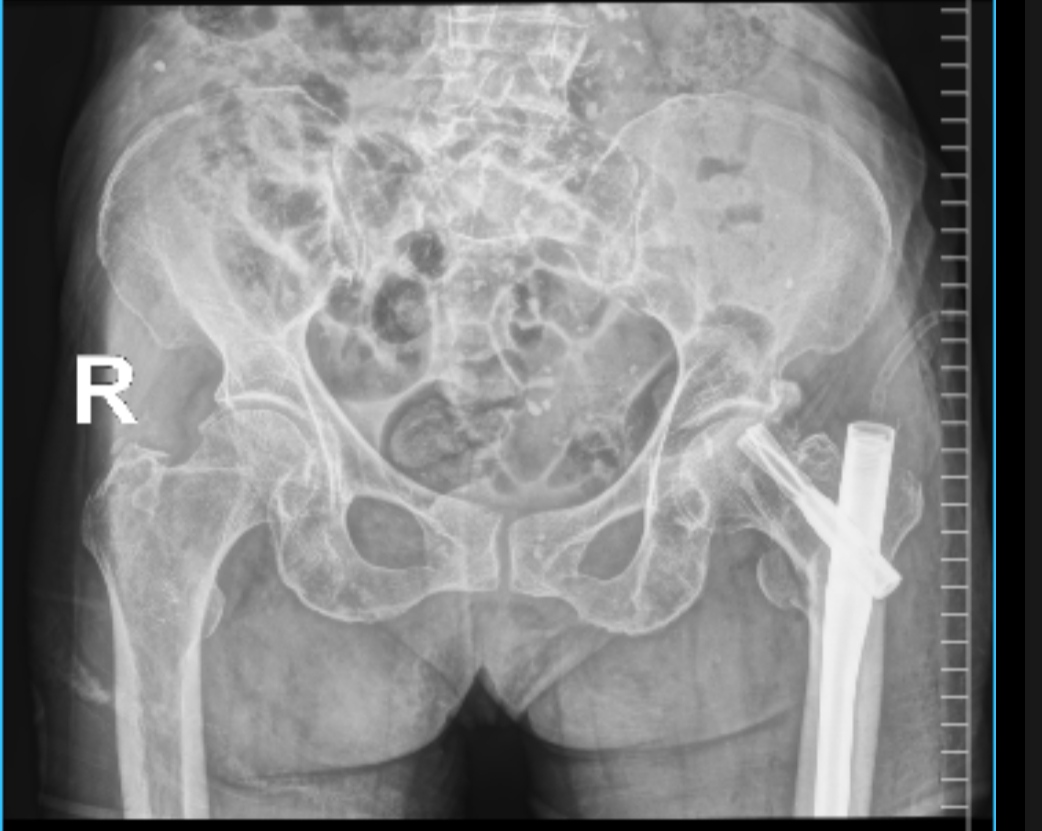

Hình ảnh chụp X- quang xương đùi của cụ N. trước phẫu thuật

Tại Bệnh viện, bệnh nhân đã được các Bác sĩ thăm khám, chỉ định làm các xét nghiệm cận lâm sàng cần thiết, chụp X-quang, … Kết quả cho thấy cụ N. bị gãy liên mấu chuyển xương đùi trái. Sau khi cân nhắc ưu, nhược điểm của các phương pháp điều trị, các bác sĩ khoa Chỉnh hình – Bỏng quyết định sử dụng phương pháp phẫu thuật kết hợp xương bằng đinh nội tủy PFNA dưới hướng dẫn của màn hình tăng sáng C-arm cho cụ N.